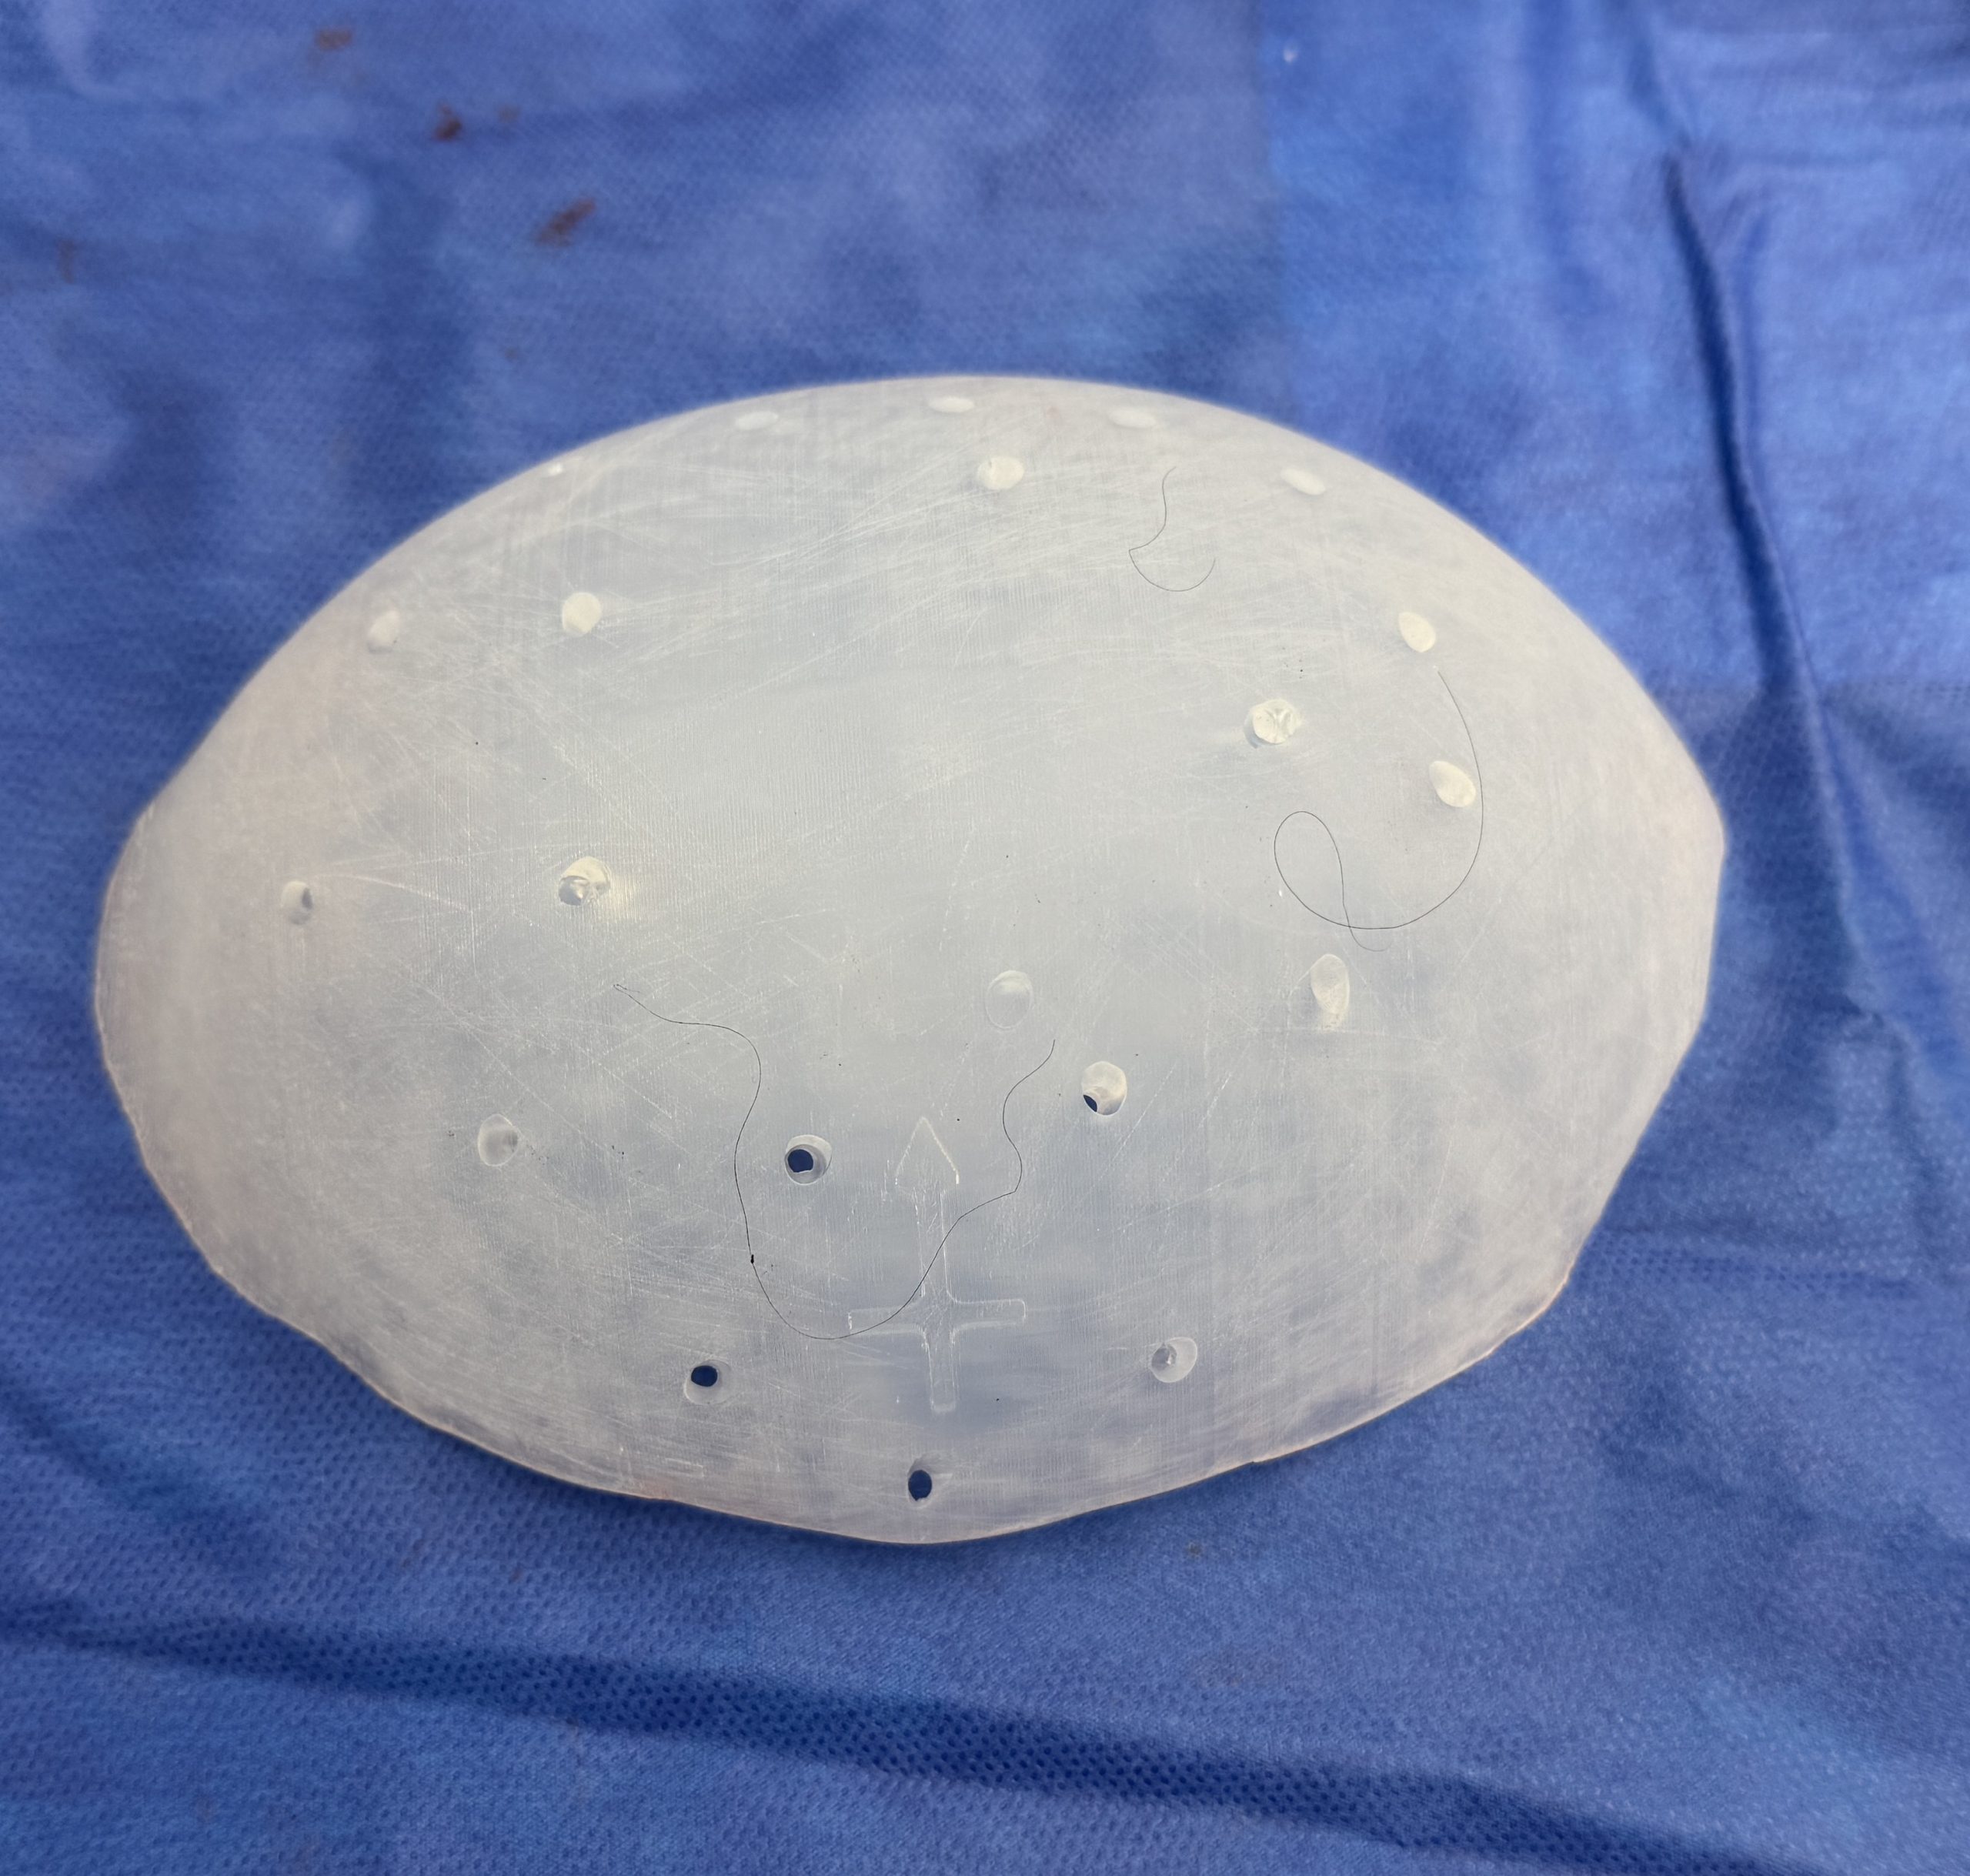

Patient 100

Desire for reshaping of an asymmetric flat back of the head in a shaved head male.

A combined back of the head reshaping procedure was done with a custom skull implant, sagittal ridge reduction and a right temporal muscle reduction.

Desire for reshaping of an asymmetric flat back of the head in a shaved head male.

A combined back of the head reshaping procedure was done with a custom skull implant, sagittal ridge reduction and a right temporal muscle reduction.